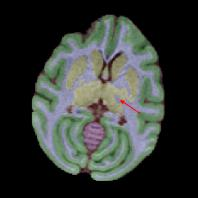

Non-human primates (NHPs) serve as critical models for understanding human brain function and neurological disorders due to their close evolutionary relationship with humans. Accurate brain tissue segmentation in NHPs is critical for understanding neurological disorders, but challenging due to the scarcity of annotated NHP brain MRI datasets, the small size of the NHP brain, the limited resolution of available imaging data and the anatomical differences between human and NHP brains. To address these challenges, we propose a novel approach utilizing STU-Net with transfer learning to leverage knowledge transferred from human brain MRI data to enhance segmentation accuracy in the NHP brain MRI, particularly when training data is limited. The combination of STU-Net and transfer learning effectively delineates complex tissue boundaries and captures fine anatomical details specific to NHP brains. Notably, our method demonstrated improvement in segmenting small subcortical structures such as putamen and thalamus that are challenging to resolve with limited spatial resolution and tissue contrast, and achieved DSC of over 0.88, IoU over 0.8 and HD95 under 7. This study introduces a robust method for multi-class brain tissue segmentation in NHPs, potentially accelerating research in evolutionary neuroscience and preclinical studies of neurological disorders relevant to human health.